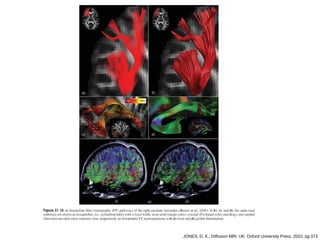

JONES, D. K.; Diffusion MRI. UK: Oxford University Press, 2010, pg 369

JONES, D. K.; Diffusion MRI. UK: Oxford University Press, 2010, pg 371

Diffusion Fiber Tratography

● Combina informações locais de glyph com

volume rendering em uma única imagem.

● Espaços curvos em 3D que representam

caminhos através da difusão.

● Streamlines, streamtubes, streamribbons,

hyperstreamlines, streamsurfaces, e mapas de

conectividade.

JONES, D. K.; Diffusion MRI. UK: Oxford University Press, 2010, pg 373

JONES, D. K.; Diffusion MRI. UK: Oxford University Press, 2010, pg 374

JONES, D. K.; Diffusion MRI. UK: Oxford University Press, 2010, pg 375

JONES, D. K.; Diffusion MRI. UK: Oxford University Press, 2010, pg 376